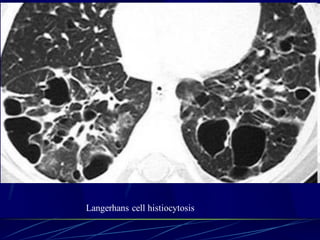

Langerhans Cell Histiocytosis

HRCT Findings

Small peribronchiolar nodules (1-5mm)

Thin-walled cysts (< 1cm),

Bizarre and confluent

Ground glass opacities

Late signs: irreversible / parenchymal fibrosis

Honey comb lung, septal thickening,

bronchiectasis

1 year later

Peribronchiolar Nodules Cavitating nodules and cysts

Langerhans Cell Histiozytosis

Key Features

Upper lobe predominance

Combination of cysts and noduli

Characteristic stages

Increased Lung volume

Sparing of costophrenic angle